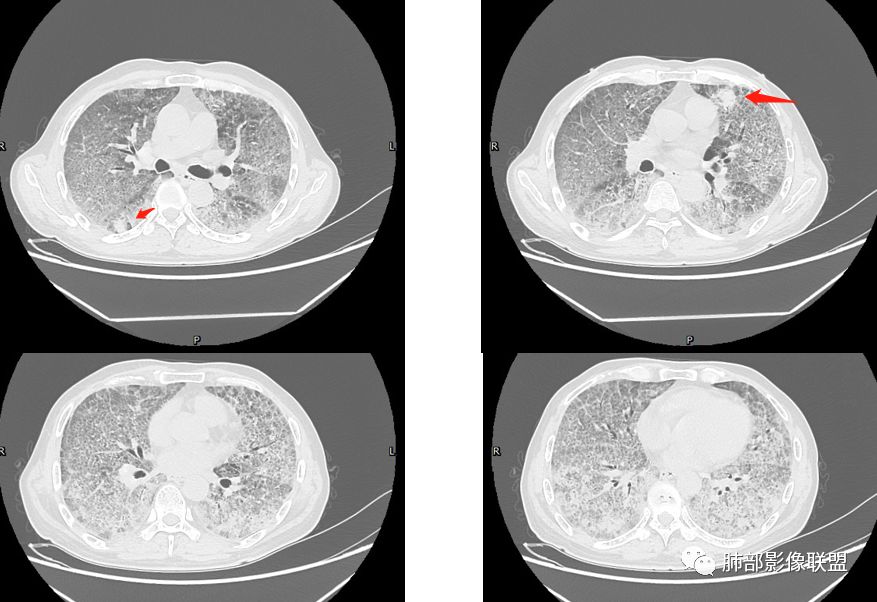

八爪:弥漫分布磨玻璃密度影,小叶间隔增厚,典型铺路石征,考虑PAP伴发感染性病变,鉴别特发性间质性肺炎,弥漫性腺癌,建议支气管灌洗;左肺上叶舌段不规则团片状阴影,显示不清,密切随访

我心飞翔:中年男性,双肺弥漫磨玻璃影,铺路石征,病灶内可见扩张支气管,CEA高,血象高,黄痰,考虑PAP并感染,腺癌待排

小景:双肺弥漫磨玻璃影,小叶间隔增厚,呈碎石路征。患者粉尘接触史,考虑PAP。左肺舌段病灶,抗感染无吸收,腺癌待排。

长沟流月去无声:有职业性工作吸入史,但影像未见典型尘肺病表现(可能防护较好),中年男性,慢性咳喘,抗感染乏效,肿标CEA较显著升高,影像弥漫GGO+网格,全肺呈“铺路石征”,中下肺另有结节斑片影像。综合考虑:PAP和弥漫肺腺癌影像存在重合,病理确诊。

小赵:中老年男性患者。慢性病程,多次咳黄痰,治疗效果一般,反复发生。CT表现为双肺弥漫磨玻璃样改变,并呈细网格样铺路石状改变,上下肺无明显差异。双下肺为主多发渗出实变,边界不清,抗炎治疗后病变吸收不明显,局部似有进展。考虑肺泡蛋白沉积症基础上合并感染。肿瘤标志物高,中老年患者,肺炎型肺癌不除外。

碎石路征,下肺为主

肺部结节

左上叶斑片状高密度影

1、GGO+网格——碎石路征

2、分布无特定位置,较随机

3、可有少许实变——部分与层厚有关

5、病灶较多时部分可见重力趋势

1.由于脂蛋白的沉积和占据,肺泡腔含气量减少,这是影像上较大范围“磨玻璃影”的基础。

2.由液体、细胞浸润和纤维组织造成的小叶间隔增厚是影像上多边形“铺路石征”的基础。

3.显眼的小叶间隔对病灶有阻挡作用是形成影像上“地图样改变”的基础。我们观察到的病灶与临近相对正常肺组织之间常常有比较清楚的分界。

4.病灶常多发,但心尖区及膈角区相对轻微。

5.部分病例显示有局部实变影